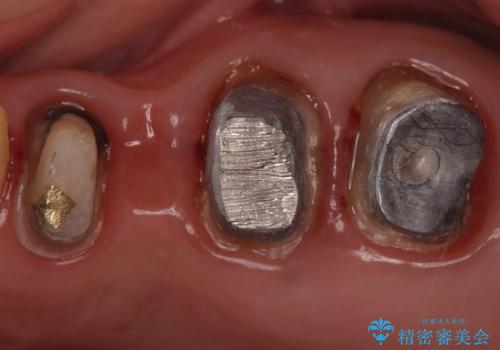

銀歯を除去し、土台の歯にに虫歯がないかを確認します。

今回は目立つ虫歯がなかったため、形を整えて白い被せものを装着しました。